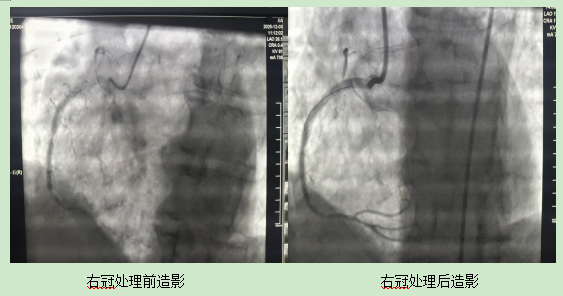

60岁的刘先生与冠心病抗争长达15年,多次的冠脉支架植入让他并没有摆脱病魔的纠缠。今年以来,严重的胸痛让他不得不入住我院心血管内科二区。通过检查发现,他的右冠支架完全闭塞,左冠向右冠逆向供血,情况很棘手。

根据患者既往有多次冠脉支架植入术、反复支架内狭窄的病史,我院心血管内科二区、心脏介入中心田致寰主任团队决定尝试一种新技术——准分子激光冠脉内斑块消蚀术。术后,患者血管狭窄问题明显得到改善,管腔面积大幅提升,患者胸痛的症状得到缓解。